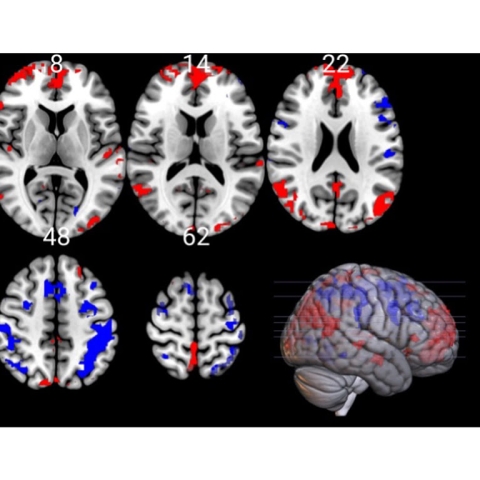

It suggests that cognitive performance is not solely dependent upon the Prefrontal Cortex (PFC) area of the brain, despite it playing an integral role in the performance of tasks.

“The PFC is highly sensitive to its neurochemical environment and is highly susceptible to stress”, explained co-lead author Juan Ignacio Badariotti from the University’s Department of Psychology.

“It regulates our thoughts, actions and emotions and is considered to be the primary part of the brain associated with executive functions.

“But our findings suggest the mechanisms behind CP may not be isolated to this area, and instead we should consider it being the product of a series of coordinated processes widely distributed across different cortical and subcortical regions.”